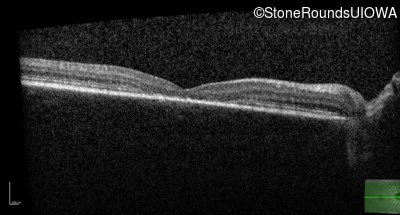

Age at visit: 13 years (Visit 2)

Age at visit: 14 years